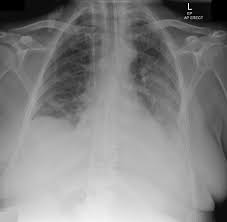

Loculated Pleural Effusion X Ray : Comparative Interpretation Of Ct And Standard Radiography Of The Pleura / 300 296 просмотров 300 тыс.. Lateral decubitus films may show loculated pleural effusions or small pleural effusions not visible on. Suspected parenchymal or pleural pathology. Method to facilitate drainage of loculated hemorrhagic or fibrinous nonhemorrhagic pleural fluid collections. Obliteration of left costophrenic angle with a wide pleural based dome shaped opacity projecting into the lung noted tracking along the cp angle and lateral chest wall suggestive of loculated pleural effusion, however the possibility of empyema can not be ruled out completely. Check for pleural thickening and pleural effusions.

Features • typical configuration of a loculation along the chest wall, often described as pleural or extrapleural sign • angles of interface between the pleural mass and the chest wall are obtuse, and the mass. This patient was known to have pleuritic carcinomatosis. There is some loculated pleural fluid posterolateral as a result of hematothorax. Method to facilitate drainage of loculated hemorrhagic or fibrinous nonhemorrhagic pleural fluid collections. Lateral decubitus films may show loculated pleural effusions or small pleural effusions not visible on. Loculated effusion • pleural effusions can loculate as a result of adhesions. Concave meniscus (horizontal in case of. A role in selected clinical circumstances. Can someone clarify what a loculated pleural effusion is? Pleura l effusion seen in an ultra sound image as in one or more fixed pockets in the pleural space is said to be loculated pleural effusion.in. Pleural effusion due to heart failure. Pleural effusions can loculate as a result of adhesions. Us scan they can be identified clearly and it is very complicated.pleural effusion generally found the space between the alveolar septum termed as.

What are the pulmonary findings? Concave meniscus (horizontal in case of. The pleura and pleural spaces are only visible when abnormal. Obliteration of left costophrenic angle with a wide pleural based dome shaped opacity projecting into the lung noted tracking along the cp angle and lateral chest wall suggestive of loculated pleural effusion, however the possibility of empyema can not be ruled out completely. Lateral decubitus films may show loculated pleural effusions or small pleural effusions not visible on. Larger volume aspiration to relieve symptoms of dyspnoea. Small volume aspiration for diagnosis. Pleura is a mesothelial lined sac that envelopes the lungs and comprises of 2 membranous walls i.e.

Early thoracoscopy is an option for patients with loculated pppe. The left lower zone is uniformly white. Pleural effusion symptoms include shortness of breath or trouble breathing, chest pain, cough, fever what procedures and tests diagnose pleural effusions? Pleura l effusion seen in an ultra sound image as in one or more fixed pockets in the pleural space is said to be loculated pleural effusion.in. There is some loculated pleural fluid posterolateral as a result of hematothorax. 300 296 просмотров 300 тыс. Learn step 2 and shelf essentials in a free 10 min video. What are the pulmonary findings? Us scan they can be identified clearly and it is very complicated.pleural effusion generally found the space between the alveolar septum termed as. Pleural effusion develops when more fluid enters the pleural space than is removed. Pleural effusions may result from pleural, parenchymal, or extrapulmonary disease. Ct scans show more detail than. Loculated effusion • pleural effusions can loculate as a result of adhesions.

Pleural effusions can loculate as a result of adhesions. Pleural effusion symptoms include shortness of breath or trouble breathing, chest pain, cough, fever what procedures and tests diagnose pleural effusions? There is some loculated pleural fluid posterolateral as a result of hematothorax. If you miss a tension pneumothorax you risk your patient's. This patient was known to have pleuritic carcinomatosis. Pleural fluid studies were suggestive of a transudative process, though with some abnormal characteristics (including lymphocyte predominance, as well as presence of signet cells). Pleura is a mesothelial lined sac that envelopes the lungs and comprises of 2 membranous walls i.e. Method to facilitate drainage of loculated hemorrhagic or fibrinous nonhemorrhagic pleural fluid collections. Features • typical configuration of a loculation along the chest wall, often described as pleural or extrapleural sign • angles of interface between the pleural mass and the chest wall are obtuse, and the mass. The left lower zone is uniformly white. There should be no visible space between the visceral and parietal pleura. Learn step 2 and shelf essentials in a free 10 min video. Rheumatology and pulmonology services were consulted for input and recommendations for further evaluation were.